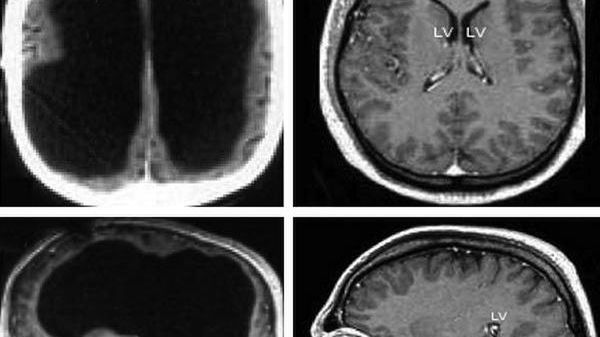

Wynik badania mózgu urzędnika

Źródło zdjęć: © The Lancet

Wyniki badania zszokowały lekarzy. Ponad 90 proc. jego głowy było wypełnione płynem rdzeniowo-mózgowym, a resztę zajmowała istota szara mózgu oraz cieniutka warstwa rzeczywistej tkanki mózgowej.

Mimo praktycznie całkowitego braku mózgu, Mathieu osiągnął IQ na poziomie 75. To liczba delikatnie niższa od przeciętnej, ale biorąc pod uwagę jego warunki to i tak jest czego pogratulować. Należy też pamiętać, że testy IQ są często niewymierne. Nawet lekkie zachwianie nastroju może mieć negatywny wpływ na wynik.